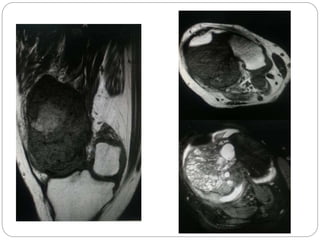

This document discusses 8 oncology cases. Case 1 involves a 40-year old female with right knee pain. Case 2 is a 28-year old male with a left subtrochantric fracture from a MVA who is now experiencing increasing left knee pain and swelling. Biopsy results showed high-grade osteosarcoma. Case 3 is a 30-year old female with breast cancer and bone metastases causing bilateral hip pain.